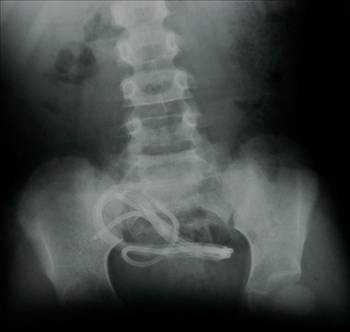

Mideye kaçan sineği öldürmek için ağza sheltox sıkmak suretiyle ölüm (İstanbul/Sultanbeyli)